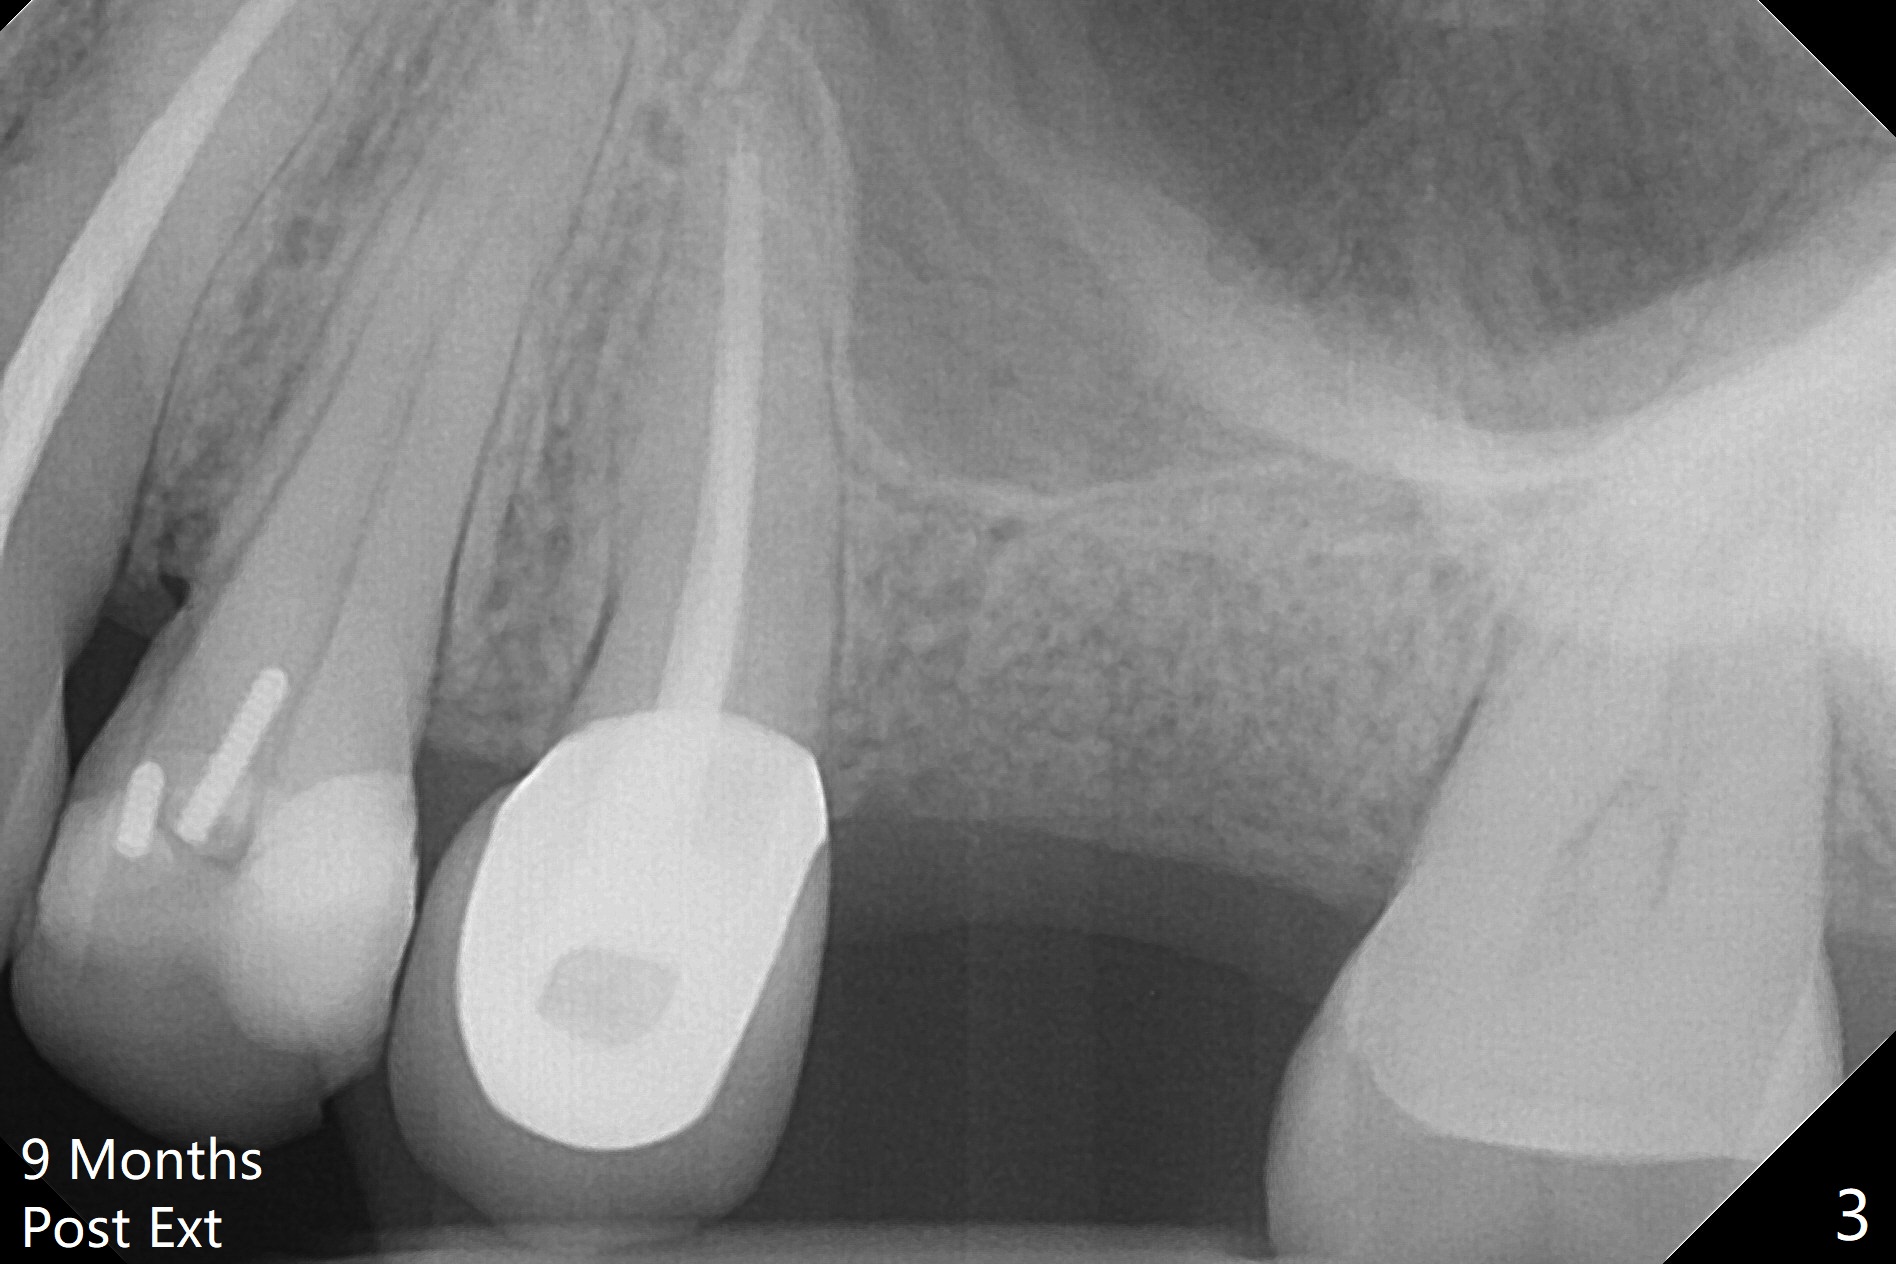

A 61-year-old woman has pain after RCT at #14 (Fig.1). Exam shows subgingival crack. After difficult extraction, allograft with Osteogen is placed in the 3 sockets, followed by Osteogen plug and 4-0 Chromic Gut Suture. The distal gingiva appears to be migrating into the center of the sockets (Fig.2 arrow). Due to insurance issue, an implant will be placed early next year. The patient returns 9 months post extraction (Fig.3). If the ridge proves to be not so wide, make incision, start osteotomy with 1.6 mm pilot drill, followed by 4.3 mm Magic Drill for 7 mm and 3.8 mm Magic Expander for another 2 mm (sinus lift, BEB, Fig.4). Otherwise start Magic Split. If the bone is dense, use drills and Expander as mentioned above with the depths 2 mm more (Fig.5), followed by Magicore. The tissue-level implant improves the crown/implant ratio over the FC. After socket healing, gingival cuff height is stable. The cuff of Magicore is easy to determine vs. immediate case.